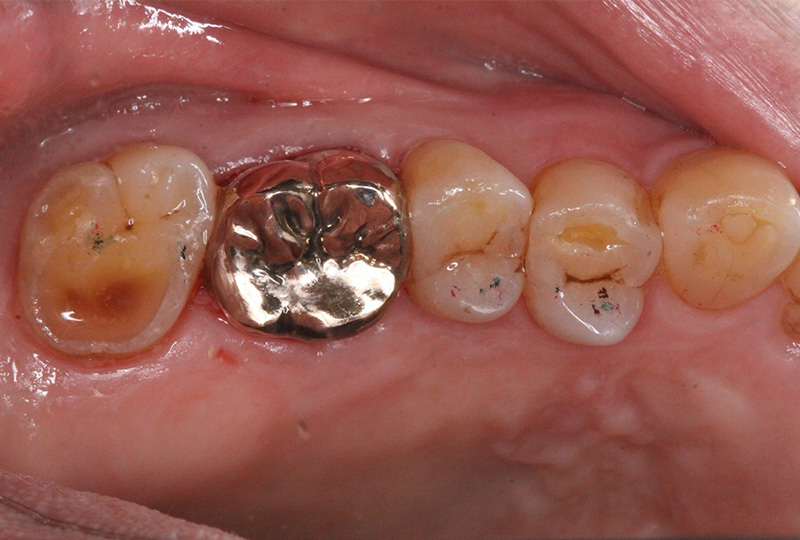

『歯のひび(歯根破折)』など通常であれば抜歯と言われるような歯の保存や歯を失った所に親知らずなどを移動させる『歯の移植』など一般の歯科医院では行わない特殊な治療も行なっております。